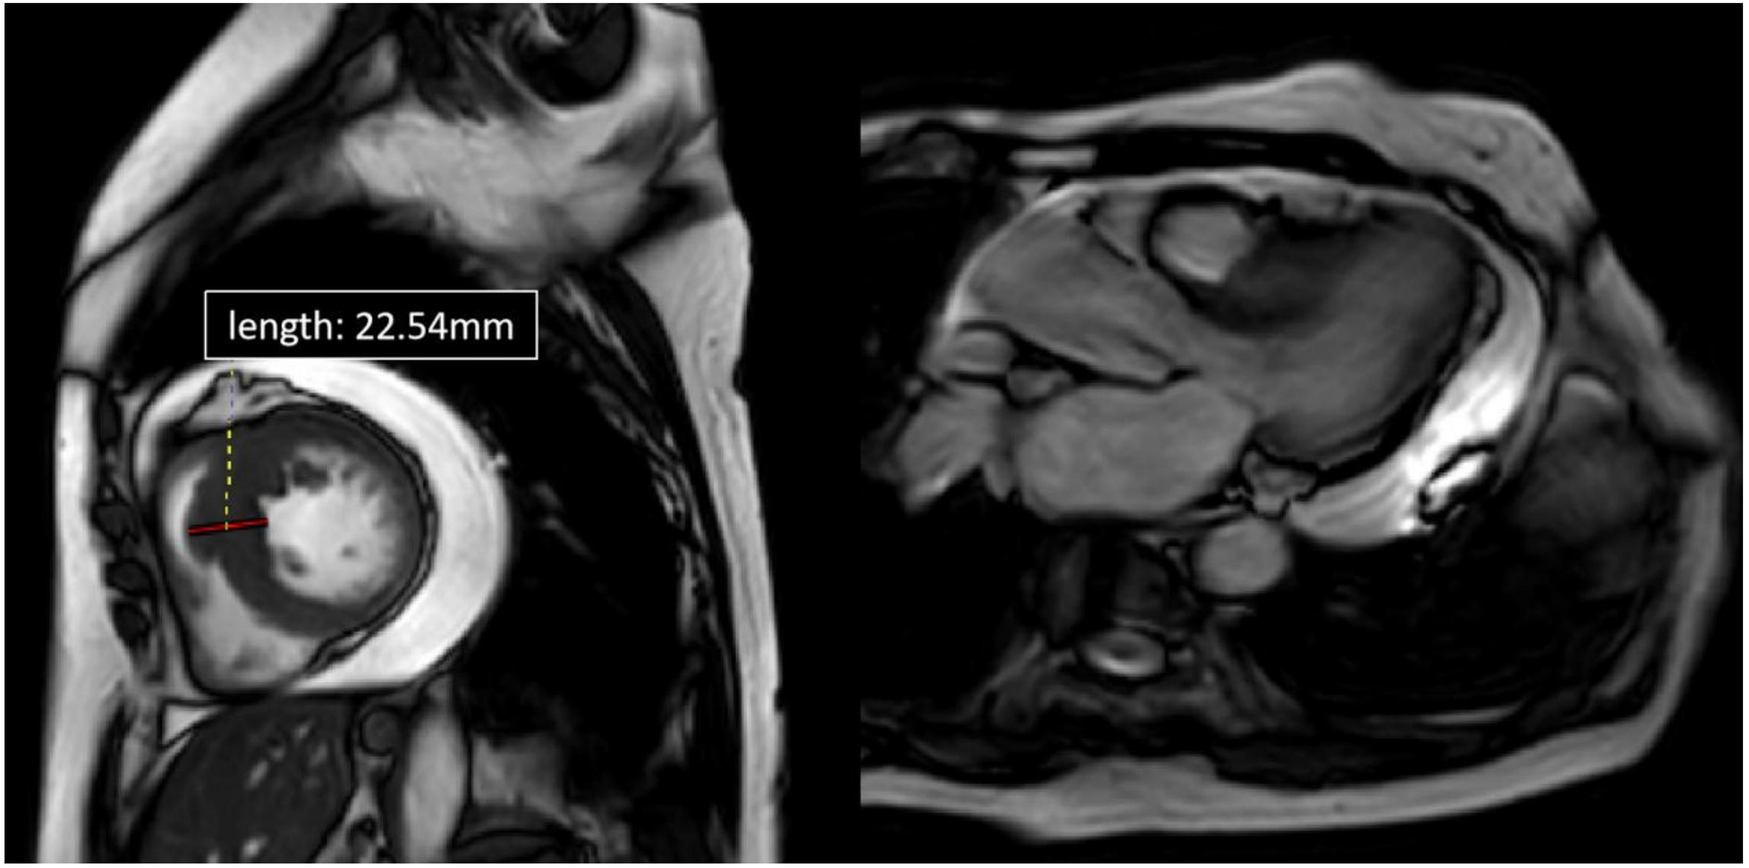

Upon admission, the patient was in a state of poor consciousness. A systolic ejection murmur was audible over the lower left sternal border, and there was evident edema in both lower limbs, though no signs of neck vein engorgement were observed. Her BNP level soared to 561.07 pg/ml. The dynamic electrocardiogram revealed severe sinus bradycardia, with an average heart rate of 43 bpm, a minimum heart rate of 32 bpm, and 1,793 episodes of sinus arrest (RR > 2 s). Both cardiac perfusion MRI (Figure 3) and echocardiography demonstrated hypertrophic cardiomyopathy and moderate pericardial effusion (Left ventricular posterior side: 16 mm, right atrial side: 13 mm). The thickest segment in the basal lower septum measured approximately 21.4 mm. After the Valsalva maneuver, the maximum flow velocity was around 201 cm/s, with a peak pressure gradient of approximately 16 mmHg.

Figure 3

Cardiac MRI of patient 2, four-chamber view. Depicted long- and short-axis cine images. The thickest segment in the basal lower septum measuring approximately 22.54 mm. The left ventricular outflow tract (LVOT) was narrowed. Pericardial effusion was observed, with the deepest area measuring about 23.5 mm.